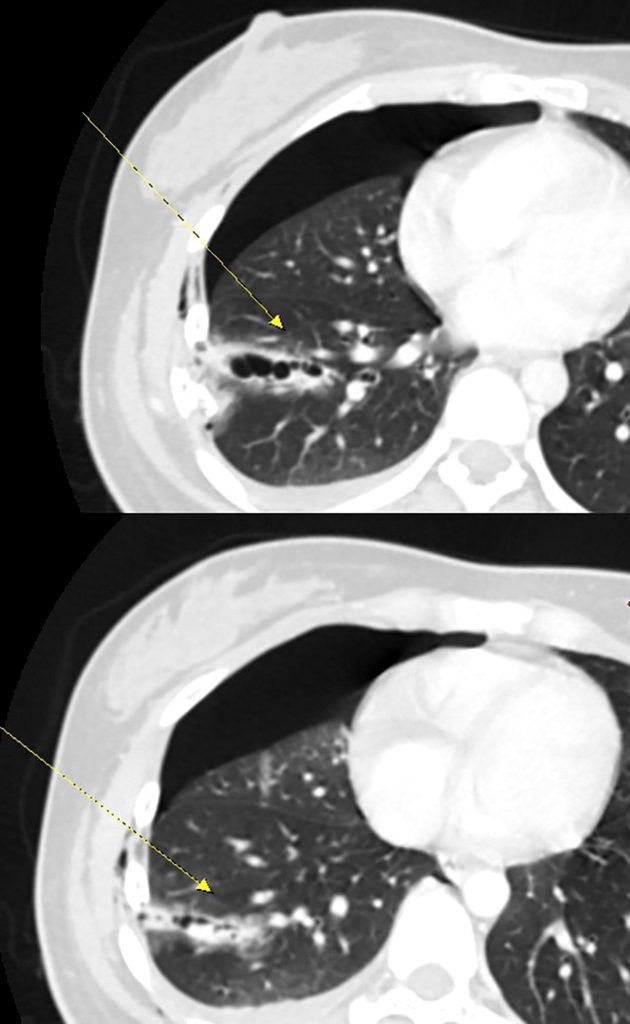

杜承哲說,胸腔損傷最怕「溫水煮青蛙」,外觀看似僅瘀青,內部卻在持續出血。患者經電腦斷層掃描,影像證實右側第5~7肋骨骨折,其中2節肋骨明顯插入肺組織,造成肺臟破裂;且胸腔內積血正持續增加,嚴重壓迫肺部擴張,單純引流可能無法止血且無法解決肋骨不穩定劇痛。如果不緊急處理,患者隨時可能由於呼吸衰竭或休克而危及生命。